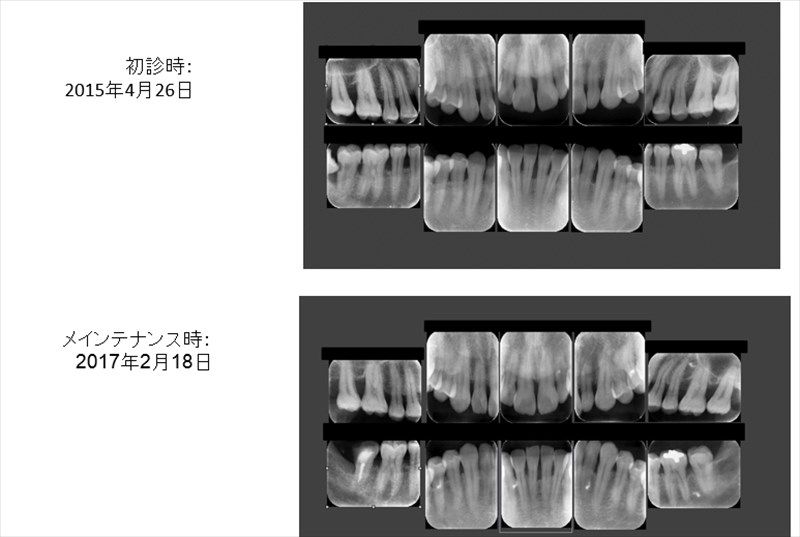

この症例は親知らずが手前の歯に食い込み他院で抜歯宣告を受けた症例です。

右下の親知らずが食い込み痛みが出ていました。

歯科ドックの診断から

①既に神経は死んでいました。

②全体的に重症の歯周病。

③親知らずが食い込む事により虫歯が根っこにできてしまっていました。

この状況から他院さんでは抜歯宣告を受けたのです。確かに抜歯されてもおかしくない状況でした。

当院ではMTAによる精密根管治療、歯肉弁根尖側移動術、骨整形により保存が出来ました。

全顎的に歯周病も改善し喜んでおられました!!